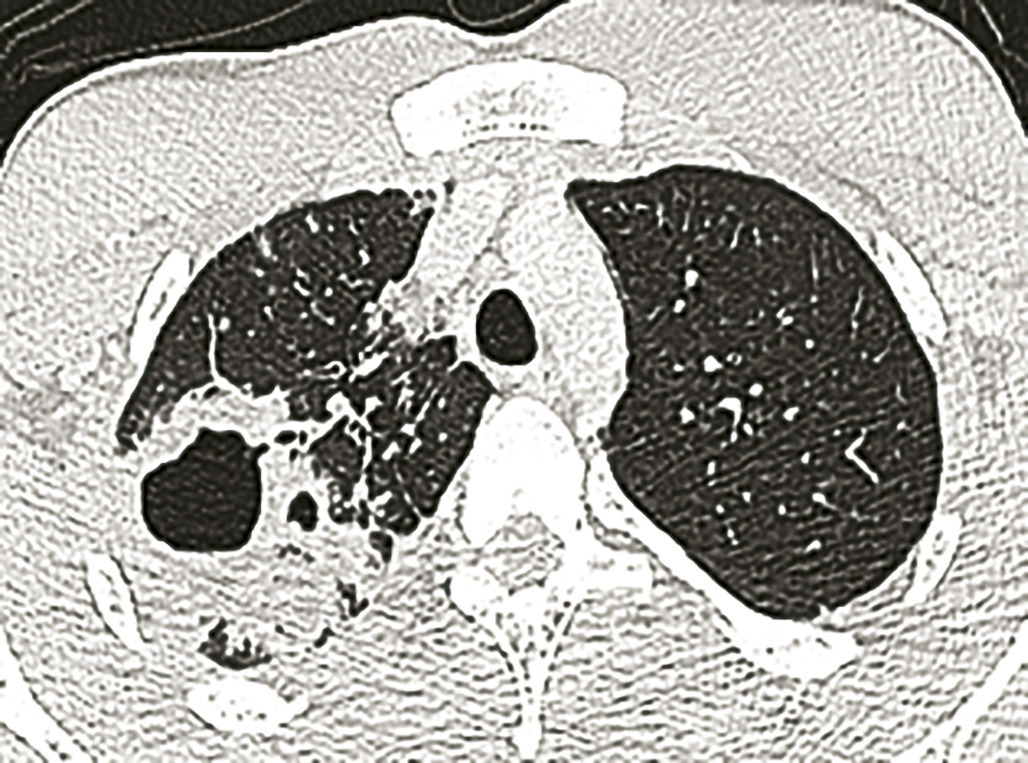

Imagerie (fig.1-4)

L’imagerie thoracique (radiographie, tomodensitométrie plus précise) révèle des opacités et modifications morphologiques de plusieurs types ± associées : atteintes bronchiolaires, bronchocèles, nodules acinaires, masses ± excavées, formes pneumoniques, rétractions lobaires, adénopathies médiastinales, pleurésies, miliaires.